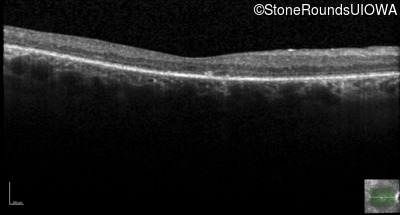

Age at visit: 59 years

OD OS